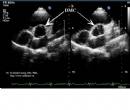

Nghiên cứu chức năng tâm trương thất trái và thất phải bằng siêu âm Doppler tim (Luận án Tiến sỹ Y học của TS. Tạ Mạnh Cường - Full text)